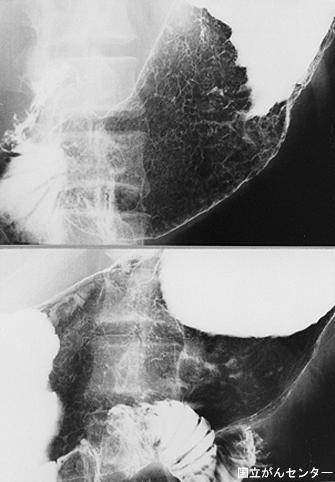

질환(병리주체)의 분류 악성 림프계종양/악성 림프종

부위(장기별) 위(부위)/2개 이상

검사방법 X-P

종양의 육안분류 0형(표재형)/IIc형(IIc)

종양의 최대경(밀리미터) 40이상

종양의 심달도 sm